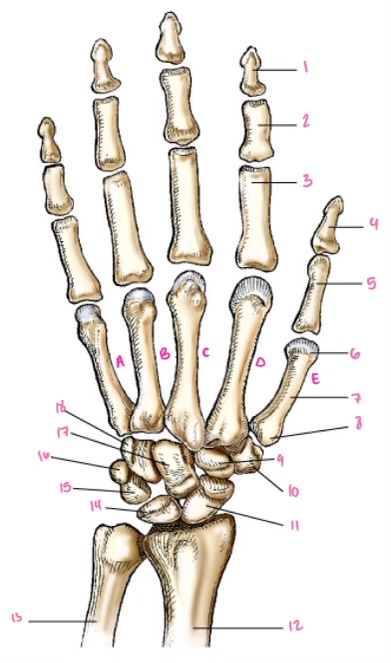

1

1

2

2

3

3

4

9

5

10

6

11

7

14

8

15

9

16

10

17

11

18

12

1

13

2

14

3

15

4

16

5

17

6

18

7

19

8

20

9

7

22

8

23

9

24

10

25

11

26

13

14

15

16

17